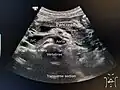

In pancreatitis, enzymes of the exocrine pancreas damage the structure and tissue of the pancreas. Detection of some of these enzymes, such as amylase and lipase in the blood, along with symptoms and findings on medical imaging such as ultrasound or a CT scan, are often used to indicate that a person has pancreatitis. Pancreatitis is often managed medically with pain relief, and monitoring to prevent or manage shock, and management of any identified underlying causes. This may include removal of gallstones, lowering of blood triglyceride or glucose levels, the use of corticosteroids for autoimmune pancreatitis, and the cessation of any medication triggers.[27]

Pancreatic adenocarcinoma is the most common form of pancreatic cancer, and is cancer arising from the exocrine digestive part of the pancreas. Most occur in the head of the pancreas.[27] Symptoms tend to arise late in the course of the cancer, when it causes abdominal pain, weight loss, or yellowing of the skin (jaundice). Jaundice occurs when the outflow of bile is blocked by the cancer. Other less common symptoms include nausea, vomiting, pancreatitis, diabetes or recurrent venous thrombosis.[27] Pancreatic cancer is usually diagnosed by medical imaging in the form of an ultrasound or CT scan with contrast enhancement. An endoscopic ultrasound may be used if a tumour is being considered for surgical removal, and biopsy guided by ERCP or ultrasound can be used to confirm an uncertain diagnosis.[27]

A normal pancreas on ultrasound. -

Identifying pancreas on abdominal ultrasonography when it is partly obscured by bowel gas. -